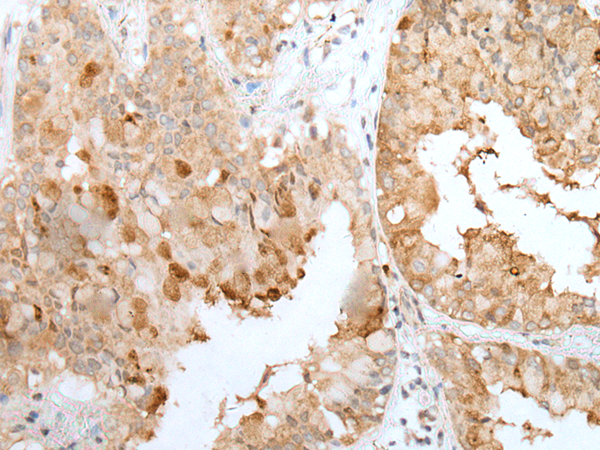

CLU/APO J |

clusterin |

IHC positive control: |

Human brain and human liver cancer |

IHC Recommend dilution: |

50-350 |